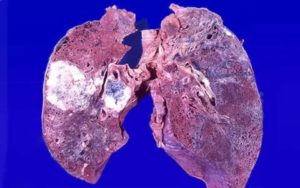

Злокачественная опухоль легких имеет тенденцию к прорастанию в соседние ткани и образованию метастазов. Виды подразделяют на локальные, регионарные и метастатические в отдаленные органы.

Третья стадия характеризуется множеством метастазов и разрастанием опухоли за пределы органа. В четвертой стадии разрастание становится более обширным, а метастазы, кроме регионарных лимфоузлов поражают отдаленные органы.

Первичная опухоль имеет эпителиальное происхождение. Рост новообразования объясняет возникающую непроходимость бронха и ведет к обтурации и ателектазам в легочном отделе, расположенном ниже. Дальнейший прогресс болезни приводит к прорастанию в соседние органы и возникновению метастазов в отдаленные.